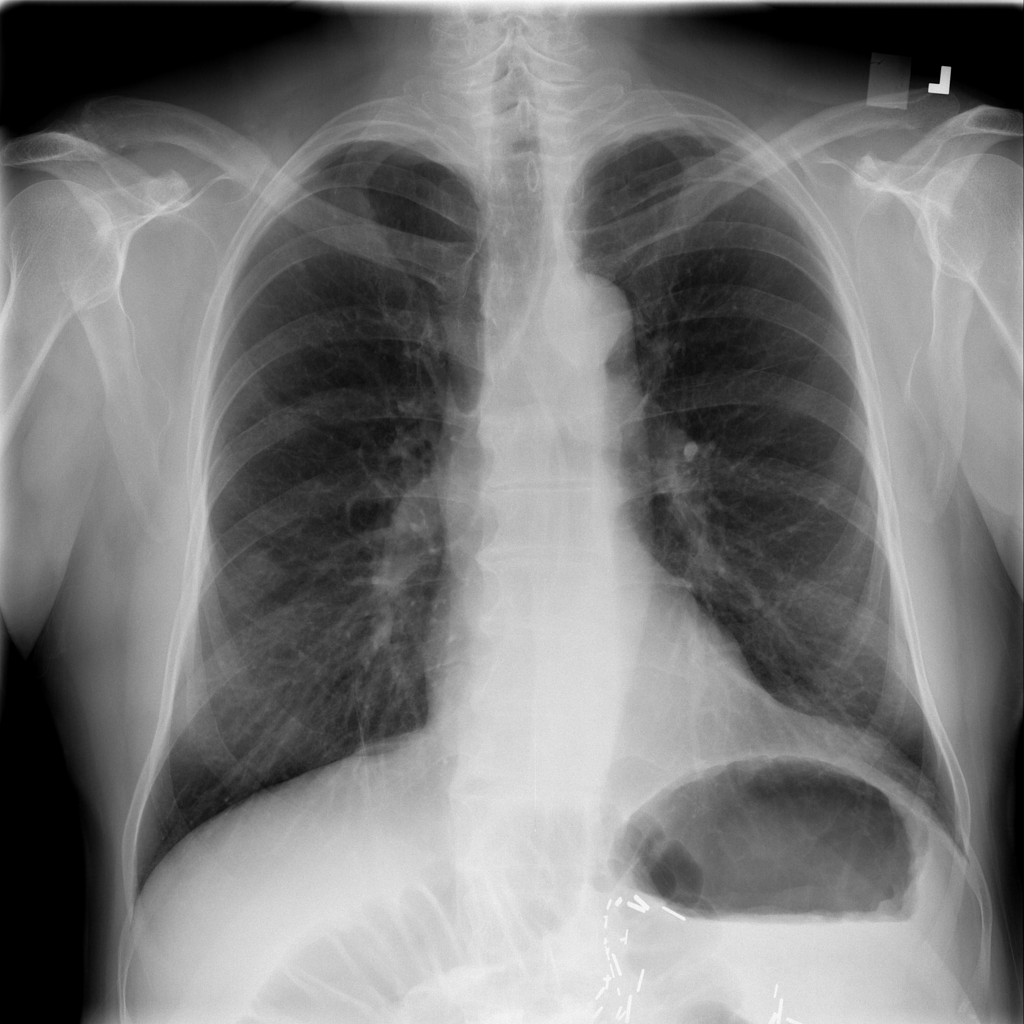

Showing up to 90 reference images for Nodule.

PAT-50E5 · IMG-000Nodule

PAT-50E5 · IMG-000

PA